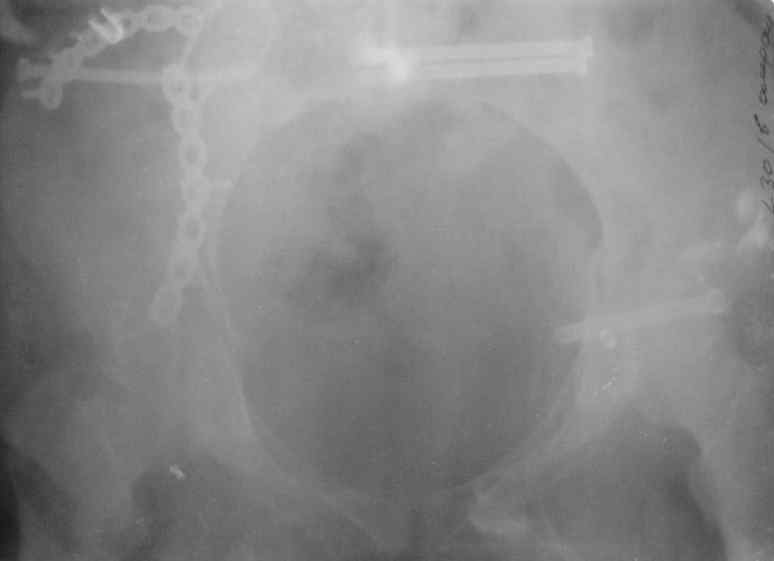

В приложении снимки при поступлении и послеоперационные год назад.

Могу сказать одно: миграция винтов и нестабильность синтеза левого подвздошно-крестцовогоо сочленения очевидна.

Мы имели ввиду перелом крестца

были использованы винты 7.2 мм, кроме того иетодика транссакральной фиксации не является общепринятой и широко рекомендуемой, но и в этих случаях они наблюдали случаи вторичного смещения

Ув.коллега.Думаю, что реостеосинтез винтами бесперспективен.Пороз, наличие большого массива рубцовой ткани, невозможность создать жёсткую фиксацию в зоне ложного сустава крестца требуют изменеия вида остеосинтеза. Тут возможны два варианта.1) Открытый остеосинтез с атупластикой и фиксацией ВЧКО задним стержневым крестцовым аппаратом.2)Тоже самое, но фиксация 2 резьбовыми штифтами типа Штейнемана за заднюю ость подвздошной кости. От выдавливания крестца кпереди следует на этих гвоздяж зафиксировать реконструкционную пластину, которая винтами синтезирует фрагменты крестца.